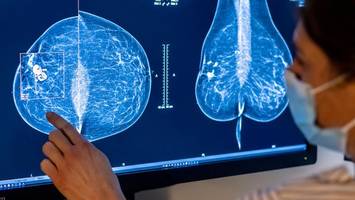

Nur rund jede zweite Frau in Berlin kommt der Einladung zum Mammographie-Screening nach. Die Gründe sind vielfältig.

Nur rund jede zweite Frau in Berlin kommt der Einladung zum Mammographie-Screening nach. Die Gründe sind vielfältig.